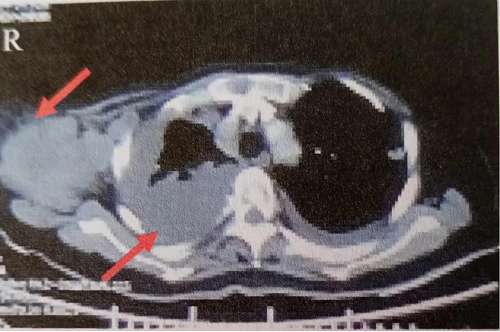

2018年7月10日行胸部CT示双侧胸廓对称,纵隔居中。右肺体积缩小,右侧胸腔可见大量胸腔积液,双侧肺野可见多发大小不一结节状高密度影,肺门及纵隔可见多发肿大淋巴结影,部分可见融合,肺动脉包绕受压,右侧胸膜可见不均匀结节样增厚,左侧胸腔可见液体密度影,右侧腋窝可见多发团块状、结节状软组织密度影,最大的约7.8cmx5.4cm,可见分叶,部分可见融合并可见液化坏死,增强扫描实性部分平均CT值约54HU(图1)。

图1胸部CT示右侧大量胸腔积液,右侧腋窝软组织密度影7.8cmx5.4cm